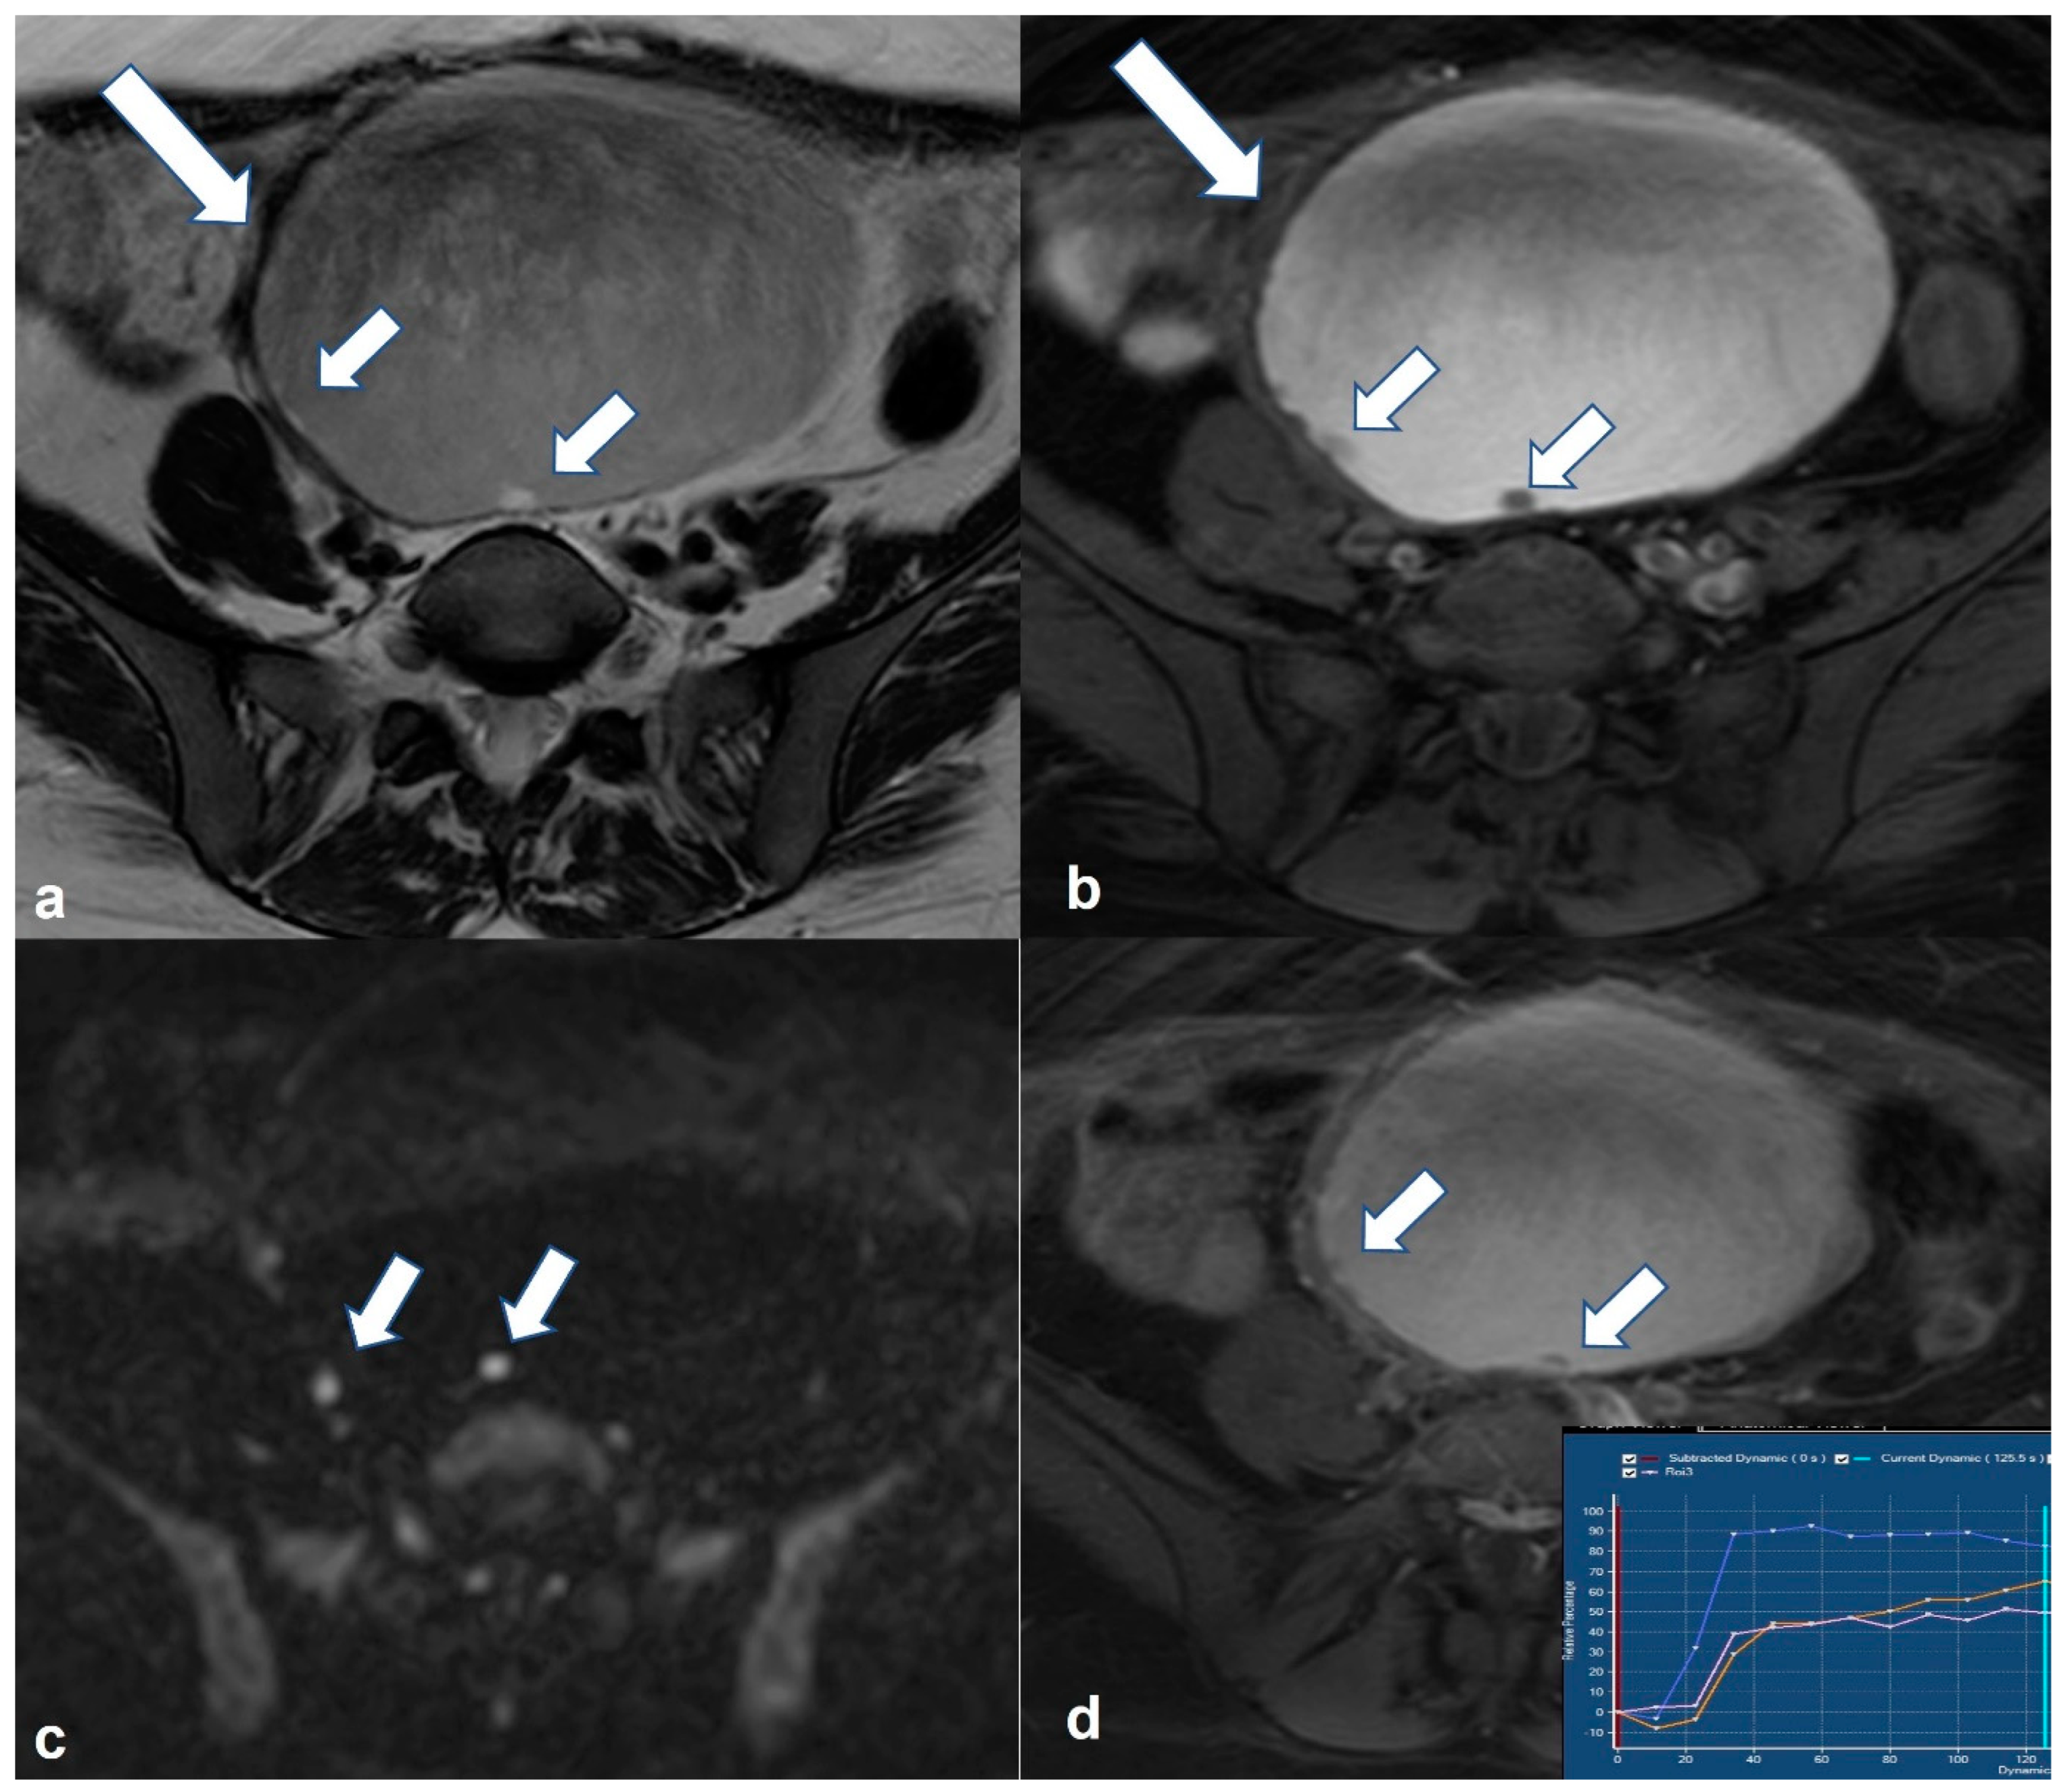

2.1.1. High-Grade Serous Cystadenocarcinoma (HGSC)

2.1.2. Serous Borderline Neoplasms and Low-Grade Serous Cystadenocarcinoma